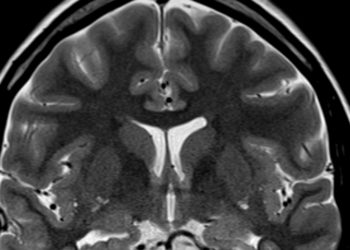

Two people can be the same age and live completely different versions of getting older. One forgets names, the other trains for marathons. Scientists at USC think they may have ...